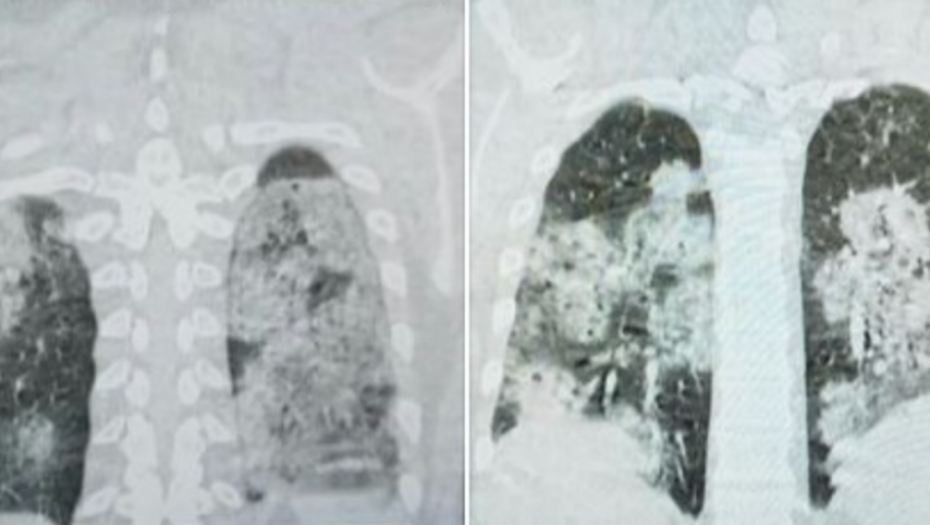

Sarajevski doktor Dragan Stevanović objavio je na Fejsbuku snimke pluća jednog od hospitalizovanih pacijenata koji je završio na kovid odeljenju.

On je objasnio da se radi o mladom, do tada zdravom čoveku koji je nepušač, a čija su pluća vidno stradala usled infekcije korona virusom.

– Za one koji ne znaju, zdrav je crni deo pluća – objavio je dr Stevanović.

– Oporavlja se. Lek je skup i ne može se nabaviti na teret zdravstvenog osiguranja. I svi ostali hospitalizovani bolesnici imaju upalu pluća. Nadati se da će što manje njih imati ovako tešku – napisao je, između ostalog, dr Stevanović.